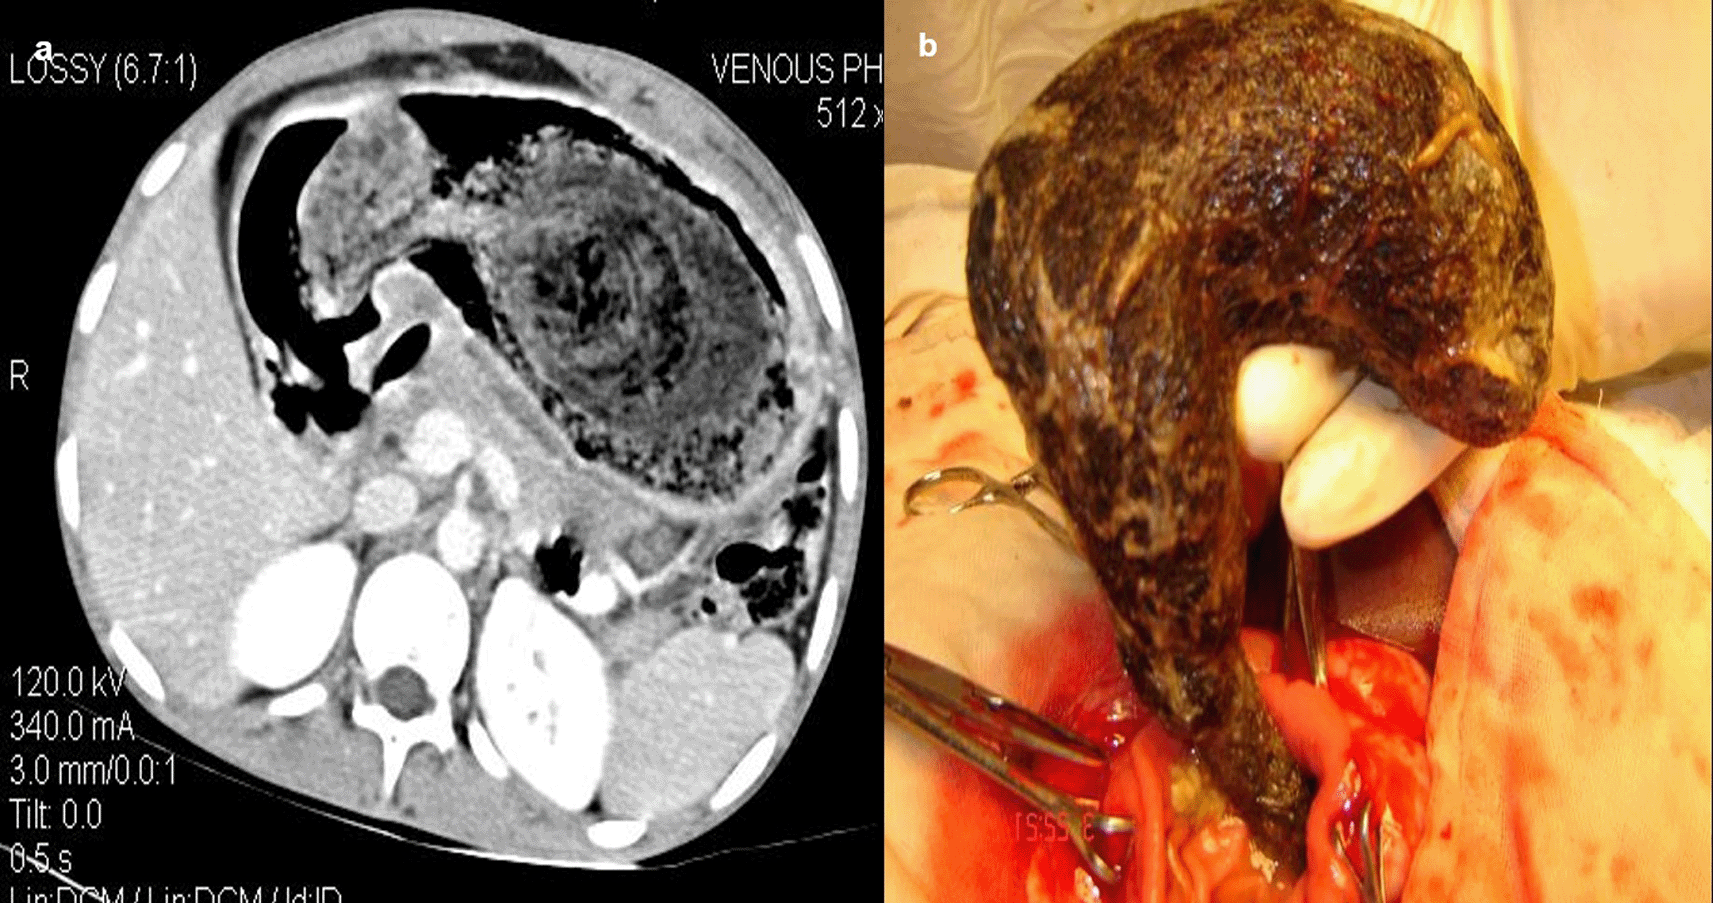

Case 4: An 18-year-old woman patient came with a history of abdominal pain and vomiting on and off for 15 days. On physical examination, the patient had tenderness in the epigastric region with a palpable lump. Visible patchy hair loss is noted on the scalp. Contrast enhanced computed tomography (CECT) reveals a heterogeneous lamellated non-enhancing soft tissue density mass (with a wide attenuation range from -70 to 70 HU) intraluminally in the stomach, conforming to its shape and extending into the antrum, pylorus, and minimally into the duodenal cap suggestive of trichobezoar. Gastrotomy revealed the ball of hair in the stomach.

When a patient cannot provide a sufficient history or has swallowed things that are not naturally radio-opaque, the diagnosis of an ingested foreign body is frequently missed. If a foreign body is suspected and is not visible on a Radiograph because of its radiolucent nature, a CT scan of the abdomen or chest may be beneficial8 (Figure 4a,b).

Gastrotomy revealed the ball of hair in the stomach (b).